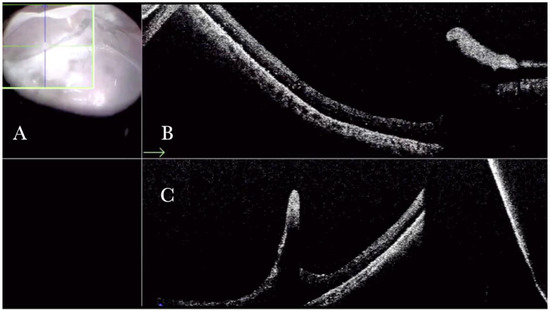

Figure 4.

(A) Microscope view of the macular area during peeling of an epiretinal membrane (ERM). The ERM is elevated. (The white box indicates the field-of-view of the OCT scan, the green circle within the white box represents the effective working distance and green and blue lines within the green circle show the vertical and horizontal scan planes). (B) Intraoperative optical coherence tomography (i-OCT) B horizontal (green arrow) scan during peeling. The ERM is elevated, and the macular profile is preserved where the ERM has been peeled. (C) i-OCT B vertical (blue arrow) scan during peeling. The ERM is elevated. The inner limiting membrane (ILM) is stretched and elevated where the ERM is peeled. The i-OCT allowed us to see the double simultaneous peeling of ERM and ILM.